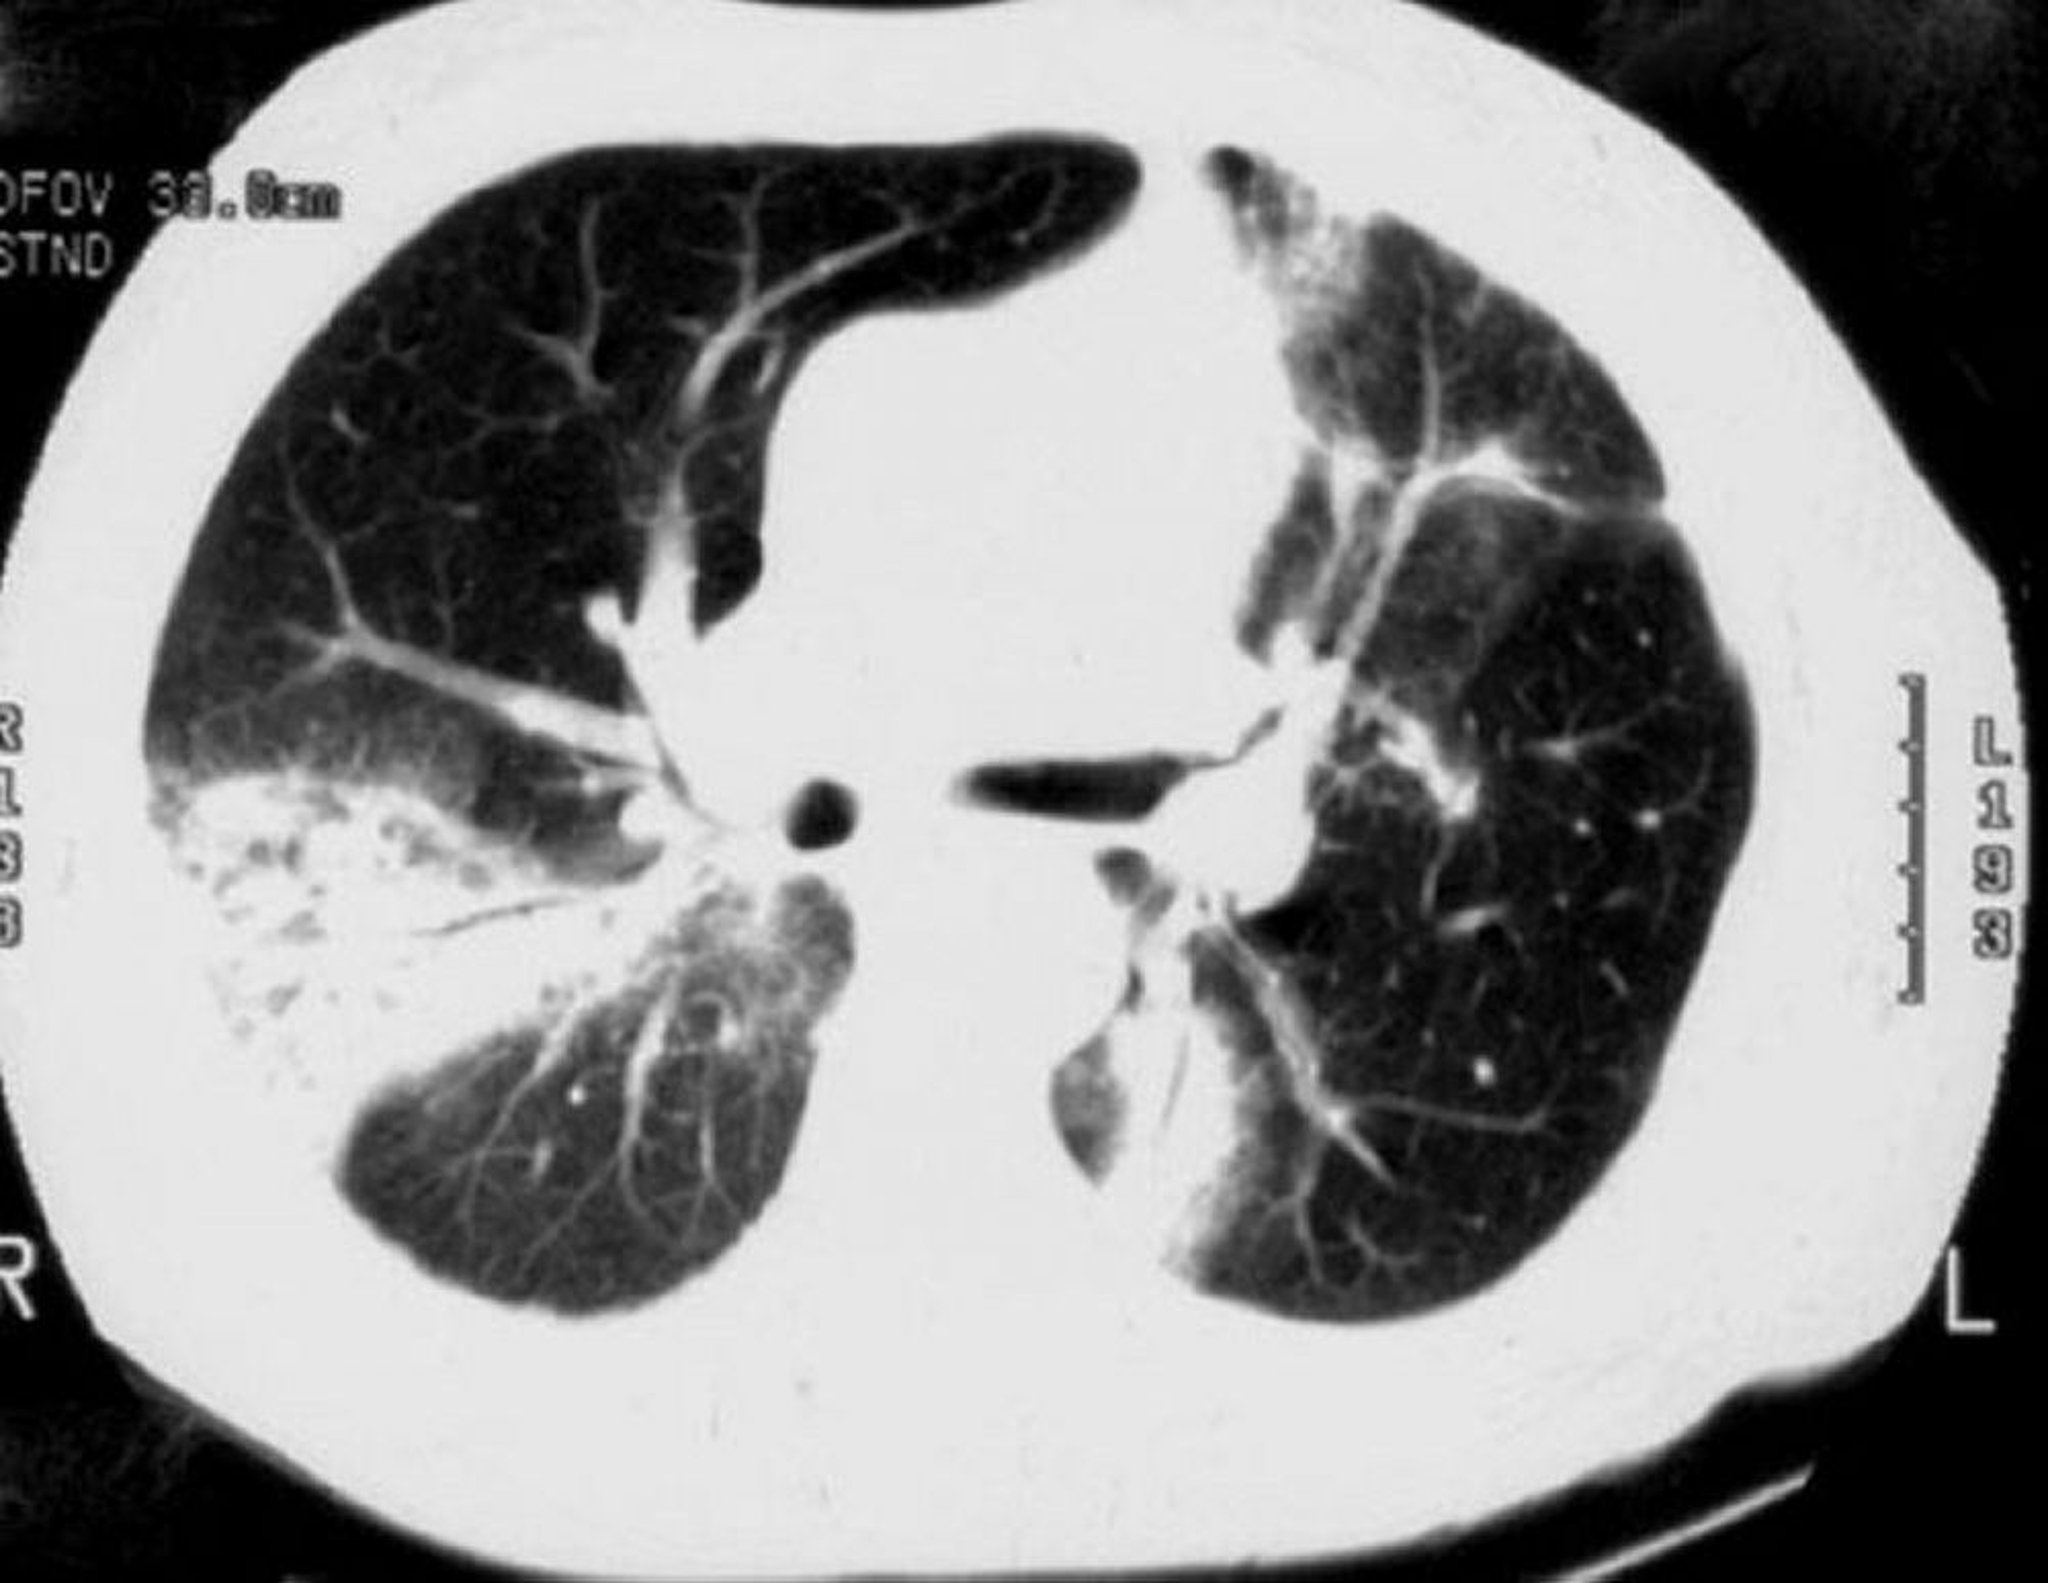

Pneumopathie cryptogénétique organisée

La TDM à haute résolution montre des plages de condensation pulmonaire, des opacités en verre dépoli, ainsi qu'une dilatation des bronches et un épaississement de leurs parois.

Image courtoisie de Talmadge E. King, MD.